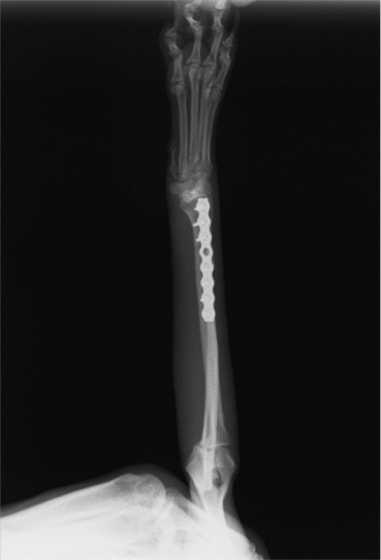

トイプードル 右遠位橈尺骨短斜骨折のALPSによる内固定

LCPは、スクリュー(ネジ)とプレート(金属の板)をロックする特殊な構造により骨折部位を固定する新しい世代のプレートシステムです。ひとつのホールでロッキングスクリューとスタンダードスクリューの使用を選択できるユニークな構造をしているため、骨折断端間の圧迫を目的とした従来型プレート固定法に加え、高い角度安定性を有するロッキングスクリューを用いた固定法の選択が可能です。従来のプレートシステムでは困難だった部分の骨折や癒合不全の症例に高い治療効果をもたらします。

7.1.5mmと薄いプレートのため、超小型犬にも使用しやすい